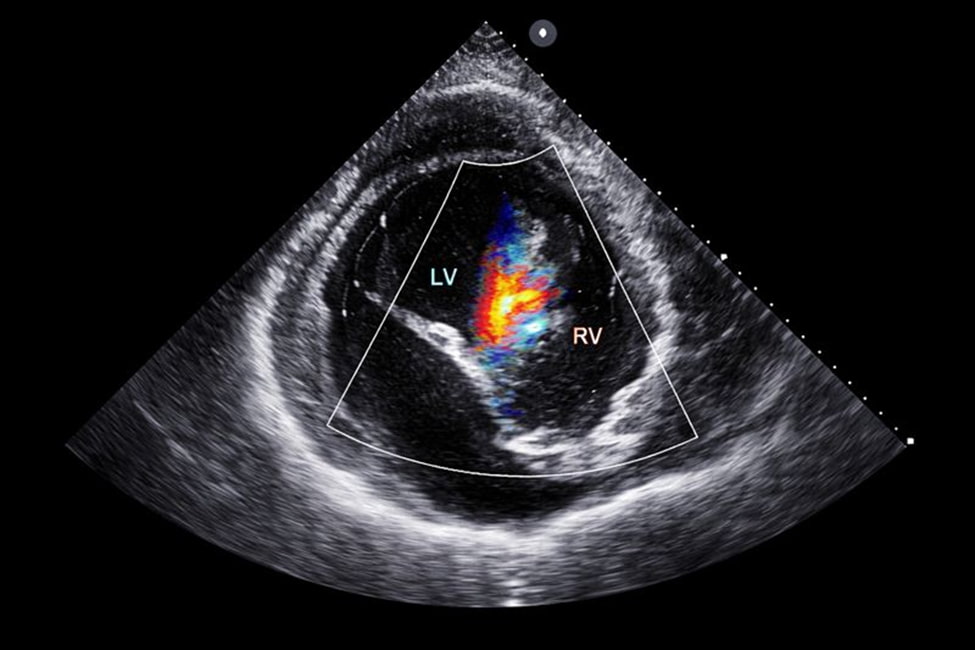

УЗИ перикарда — это ультразвуковой метод, направленный на изучение оболочки, окружающей сердце, а также пространства между ее листками. Исследование позволяет получить представление о морфологических изменениях и функциональном влиянии перикарда на сердечную деятельность.

Процедура проводится как самостоятельное обследование или в рамках комплексной эхокардиографии. В норме между листками перикарда содержится минимальное количество жидкости, обеспечивающее скольжение. Любое дополнительное скопление может указывать на патологический процесс, что и помогает выявить ультразвуковая диагностика.

УЗИ перикарда позволяет детально оценить толщину и структуру листков, а также наличие выпота. Специалист анализирует объем и распределение жидкости, сопоставляя данные с показателями нормы.

Метод дает возможность выявить перикардиальный процесс, определить степень его выраженности и влияние на общее состояние пациента. Полученные данные имеют значение при выборе тактик наблюдения и лечения.

Во время обследования используется режим ЭхоКГ, который позволяет визуализировать перикард в реальном времени. Процедура проходит спокойно, не вызывает болевых ощущений и хорошо переносится пациентами любого возраста.